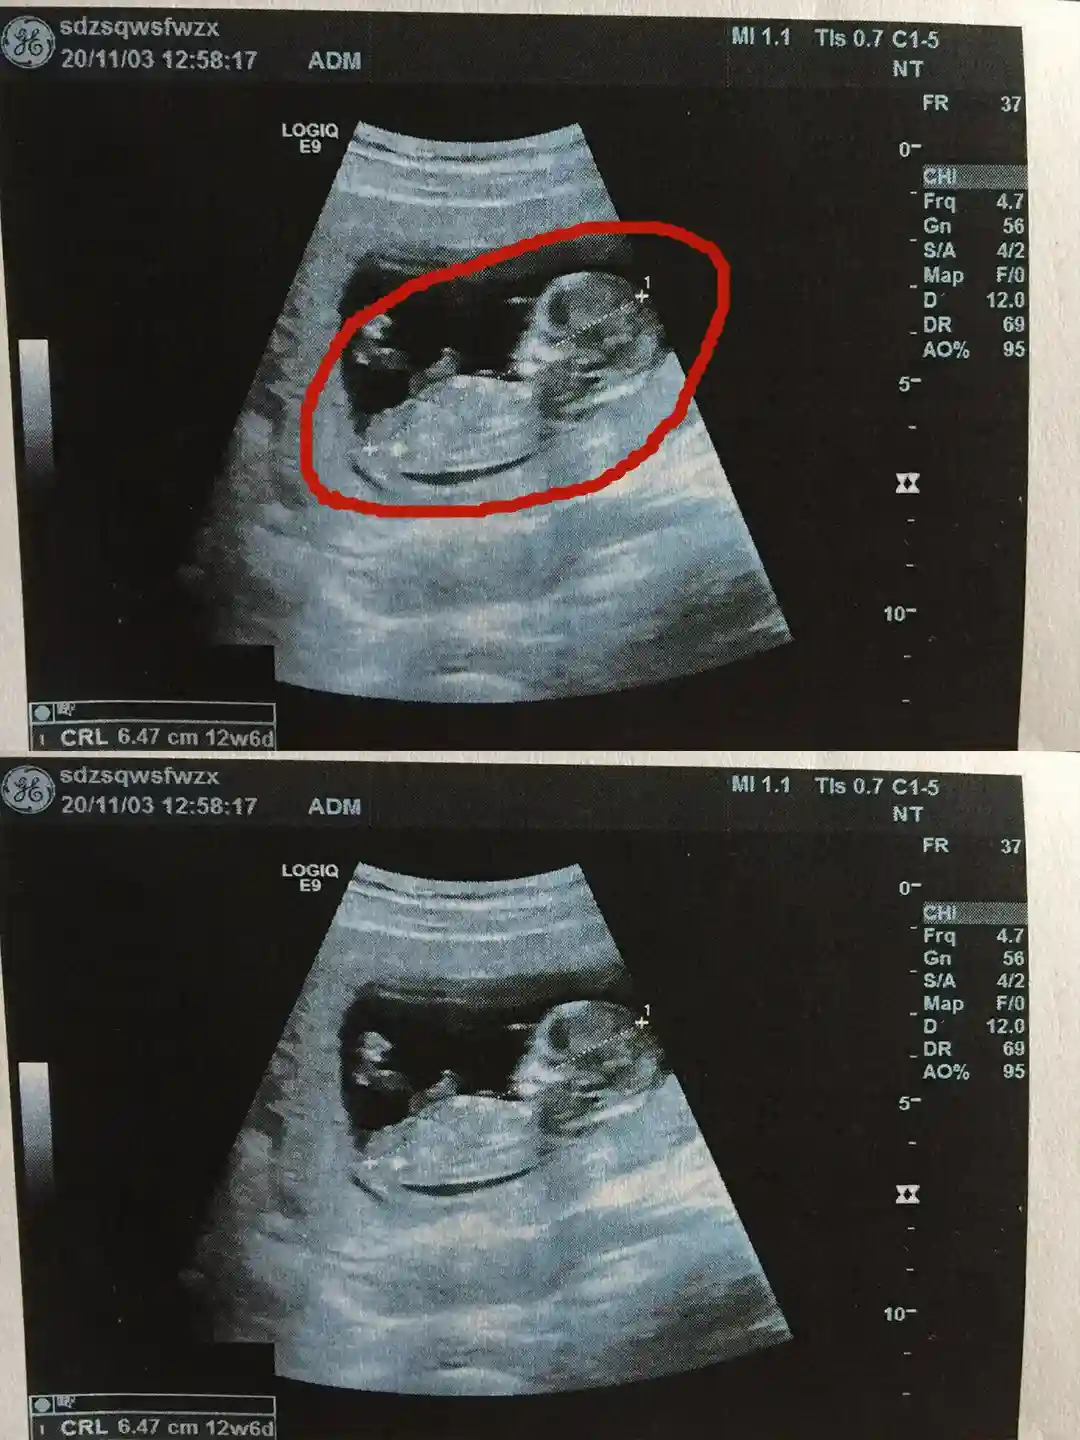

结婚后,我们也商量着备孕,但是一直没要上。感觉是因为我的原因,去j查,还真是,多.囊,难受孕,当时就特别后悔,为什么当时没有及时的看。

反复治辽无果,于是开始自己调里,现在成功好孕了,把我的经验给大家分享。